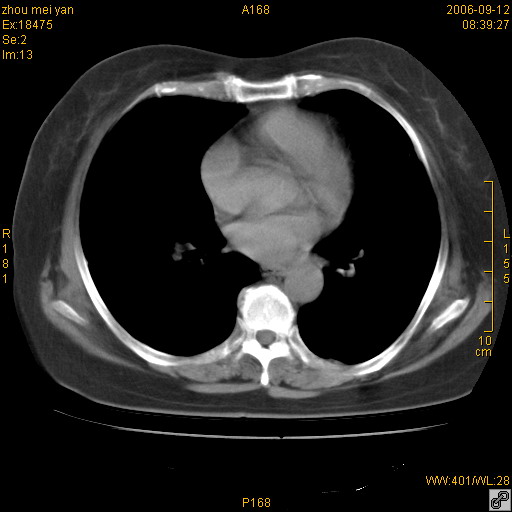

患者、女、55岁。因心率失常住院检查ct发现胸部多发结节。腹部b超肝、胆、胰、脾、肾、子宫附件未见异常。无结核病史,无粉尘接触史。请大家来会诊。谢谢!

病变位于胸膜,多发结节,边界清楚,内见小结节状钙化。其它未见异常。

双侧胸膜多发结节,形态不规则,边缘较清楚,每一个结节中心似乎都有钙化点的特征,与胸膜广基相切。临床无结核病史,无粉尘接触史。

胸膜间皮瘤可能性大。在气管隆突前可见一肿大淋巴结影。

影像表现十分有特点:双侧肋胸膜及膈胸膜广泛散在分布大小在2至6mm左右,较大病灶中心可见钙化。

考虑恶性胸膜间皮瘤可能性大,病灶位于胸膜,以宽基地与胸膜相连,呈结节样改变,部分病灶内可见点状钙化影。请各位老师多多指导!

双侧肋胸膜及膈胸膜广泛散在分布大小不等结节影,较大病灶中心可见钙化。